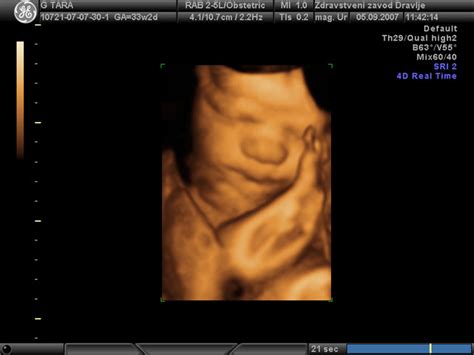

- 3D/4D ultrazvok: Omogoča bolj podroben vpogled v razvoj ploda, vključno z oceno plodovega srca, organskih sistemov, obraza in ocenjevanje teže ter napovedi porodne teže. Cena se giblje med 60 € in 120 €, pogosto z možnostjo zapisa na USB ključek ali CD za doplačilo (10 € - 15 €).